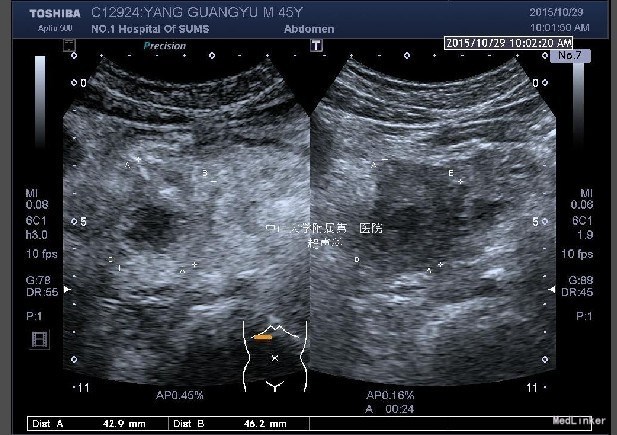

查体:身目重度黄染,上腹部轻压痛; 辅助检查: 白细胞WBC:10.96; 血红蛋白Hb:145g/L;血小板PLT:241x10^9/L 丙氨酸氨基转移酶ALT 357 U/L ;天冬氨酸氨基转移酶AST 191 U/L;白蛋白ALB 40.9 g/L ;总胆红素TBIL 151.2 umol/L;直接胆红素DBIL 85.8 umol/L 肿瘤标记物: 甲胎蛋白(AFP) 5.00 ug/L 0.00 - 20.00 ;癌胚抗原(CEA) 9.19 ug/L ↑ 0.00 - 5.00 ;CA125 71.00 U/mL ↑ 0.00 - 35.00 鳞癌抗原(SCC) 0.90 ug/L 0.00 - 1.50 ;CA19-9 〉12000.00 U/mL CT:平扫胰体尾部萎缩,胰头区不规则肿大,局部可见类圆形软组织肿块影,大小约44×43mm,边界模糊,内部密度不均,其内可见斑点状钙化灶,并见更低密度区。增强扫描正常胰腺组织明显强化而肿物轻度强化,显示较清楚;强化不均匀,中央有低密度坏死区。肿块与十二直肠降段分界不清,病变包绕肠系膜上静脉,血管见充盈缺损影,胰头周围及腹膜后见肿大的淋巴结影。、、、 1.胰头癌,侵犯十二指肠降段及肠系膜上静脉,胰周及腹膜后多发淋巴结轻度肿大。 2.肝S7病灶,高度怀疑转移瘤。 超声造影提:胰头病变:考虑胰头Ca。 肝S7病变:考虑MLC。 肝内外胆管弥漫性扩张。胆囊壁增厚。腹膜后淋巴结肿大。脾脏超声检查未见异常。